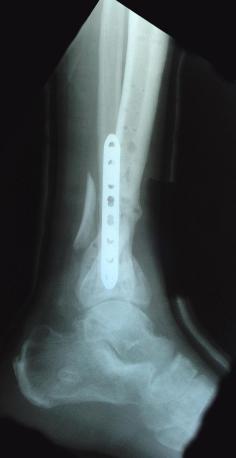

Pre-corrective surgery X-Rays of the damaged right & left legs / ankles

These x-rays were taken at Dr Armendariz’s office, just prior to performing any corrective surgery. As can be seen in these images,

there was no tibia bracing provided by Dr. Keller. Liam was released from Dr Keller’s care with instructions that full weight bearing could

be accomplished within 2 months of Keller’s last surgical procedure. The best example to examine is the second image (from the left) of the

top how. Notice how the bones that should be aligned with the tibia are in fact on the other side of the leg. The third image shows how badly

Liam’s left foot was twisted as a result of the pool placement of the external fixation. What is not obvious is that the screw at the bottom

of the plate on the right fibula missed being screwed into the plate.